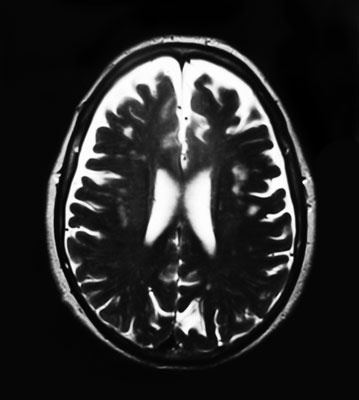

МРТ-снимок мозга девушки, которая жалуется на периодические головокружения. Кроме того, она не может сразу подобрать нужные слова. В правой лобной доле (если смотреть на фото так, как есть, – то слева) видна лимфатическая мальформация.